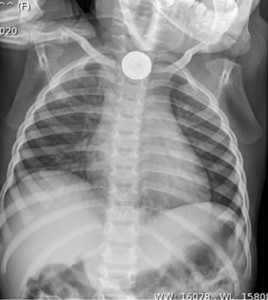

During the last decade, there has been a dramatic increase in the number of button battery ingestions and associated injuries in small children and infants. This is related to the growing use of large size (< 20 mm) lithium batteries in electronic devices. The batteries are now used in a wide range of devices, including remote controls, computers, musical greeting cards, and toys. The larger batteries, when ingested, will often lodge in an infant’s or toddler’s esophagus, and may create severe injury, including tissue necrosis, in just two hours. The combination of the children’s easy access due to battery compartment security problems, larger battery size, and higher power voltage (3 V) leads to these severe injuries. The most comprehensive data on button battery ingestion comes from cases reported to the National Battery Ingestion Hotline (NBIH) and nationwide U.S. Poison Control centers.1-3 There are likely more than 3,000 ingestions each year. While most ingestions are benign as the batteries pass into the stomach and lower gastrointestinal system without incident, a smaller, but substantial number may lodge in the esophagus and cause severe injuries in a short time. These include minor burns, moderate injuries (esophageal strictures), major injuries (traumatic tracheal-esophageal fistula, vocal cord paralysis), and even death. Death is often related to direct erosion of the battery into the aorta with a massive hemorrhage. In fact, Litovitz reported in Pediatrics in 2010 on 221 minor, 74 moderate, 19 major, and one death from ingestion as reported to the National Poison Control Center in Washington, DC.1 This trend has seen a 6.7 fold increase in the number of major or fatal injuries in the last 25 years. Otolaryngologists are often called to remove these batteries and treat the injuries. Since most severe injuries result from un-witnessed ingestions, prevention may be the best overall solution. New ENT Exam Video Series Released Button Battery Task Force In 2012, the American Broncho-Esophagological Association (ABEA), led by President Peter J. Koltai, MD, in conjunction with the American Academy of Otolaryngology-Head and Neck Surgery (AAO-HNS) and the American Academy of Pediatrics (AAP), formed the Button Battery Task Force to address this problem. The Task Force, chaired by Ian N. Jacobs, MD, has representatives from multiple medical organizations and product safety experts. The task force aims to find solutions to the button battery problems using a multi-pronged approach, which includes: Voluntary industry design standards Public awareness and marketing Development for funding activities Legislative and regulatory support The Task Force is working with industry on safer redesign as part of voluntary industry change. This includes working with battery makers, such as Energizer, on voluntary design changes to increase safety with safer batteries, better packaging, and improved labeling. On January 18, 2013, the Task Force met in Chicago with a number of key industry stakeholders to discuss solutions to the problem. It is also collaborating with Energizer and the AAP to develop public awareness materials intended to be displayed in pediatrician’s offices, children’s hospitals, and pediatric healthcare facilities across the country. Four current members of the Task Force, Toby Litovitz, MD; Kris R. Jatana, MD; Steve Krug, MD; and Don Mays, presented to the U.S. Consumer Product Safety Commission (CPSC) in March 2011. The Button Cell Battery Safety Act of 2011 (S.1165) that followed failed to advance in the 112th Congress. In September 2012, the Task Force met with legislators in Washington, DC, for early discussions on future political strategies and intends to have a meeting with the CPSC this spring to discuss future regulatory enforcements for areas of concern like compartment security. The ultimate goal is to decrease the incidence of button battery ingestion injuries with a multi-faceted approach and change the lives of innocent children who come into contact with these devices. References Litovitz T, Whitaker N, Clark L, White NC, Marsolek M. Emerging battery-ingestion hazard: Clinical implications. Pediatrics. 2010;125(6):1168-1177. Sharpe SJ, Rochette LM, Smith GA. Pediatric battery-related emergency department visits in the United States 1990-2009. Pediatrics. 129(6):1111-1117. Litovitz T, Whitaker N, Clark. Preventing battery ingestions: an analysis of 8648 cases. Pediatrics. 2010; 125(6):1168-1177.